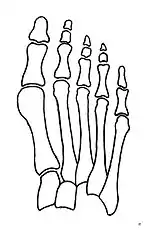

Primus varus deformity is the leaning of the first metatarsal bone away from the second metatarsal and towards the opposite foot (Fig. 1). As it leans over, its head sticks out to form the bunion bump and it also widens the forefoot to cause shoes feeling too tight. Thus when bunion pain becomes unmanageable, surgical correction is to narrow the forefoot by repositioning of the first metatarsal head back to its normal position. This can be done by osteotomy (bone-breaking), soft tissue (non-osteotomy) or fusion techniques.